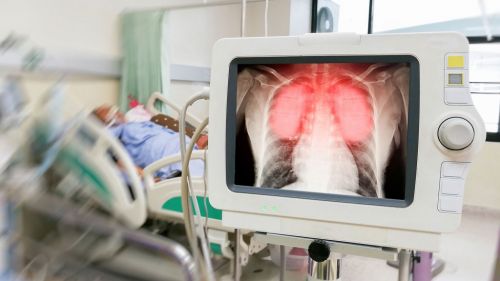

Воспаление легких – самое серьезное осложнение коронавируса. На рентгеновских снимках виден так называемый эффект матового стекла. При этом, когда человек выздоравливает, ему необходимо какое-то время на восстановление функции легких.

- множественные помутнения на снимке (эффект матового стекла);

- утолщение стенок сосудов и периферическое распределение очагов.

Снимок легких при коронавирусе

Журнал Radiology опубликовал снимок легких 33-летней китаянки. Женщина была госпитализирована с температурой 39 градусов. На рентгене были множественные помутнения. Через три дня ситуация усугубилась – на втором снимке видно, что область «матового стекла» стала больше.